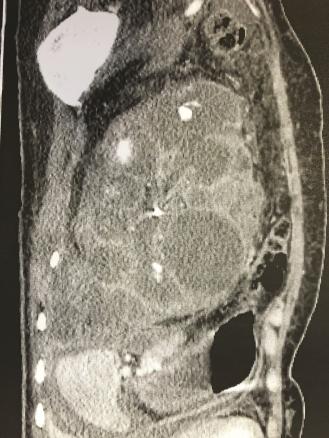

Cette patiente de 33 ans consultait pour des douleurs abdominales fébriles (38,9 °C). L’examen clinique notait une défense du flanc gauche sans autres anomalies. Le bilan biologique montrait des leucocytes à 21 740 /mm3 et une CRP à 312 mg/L. La tomodensitométrie (TDM) abdominopelvienne montrait une hypertrophie rénale gauche de 20 cm de grand axe et une dilatation des cavités pyélocalicielles avec de multiples abcès et cavités liquidiennes en faveur d’une pyélonéphrite xanthogranulomateuse diffuse (fig. 1 et 2). Une antibiothérapie par ceftriaxone, métronidazole et gentamycine était instaurée puis adaptée à l’antibiogramme (Proteus mirabilis multisensible) par amoxicilline seule. En l’absence d’amélioration biologique et à la TDM au 5e jour, une néphrectomie gauche était réalisée (fig. 3). L’anatomopathologie notait un tissu de granulation riche en cellules xanthomateuses et un infiltrat inflammatoire polymorphe remplaçant le parenchyme rénal.

La pyélonéphrite xanthogranulomateuse est une forme rare de pyélonéphrite (0,6 à 1,4 %) touchant surtout les femmes (3/1) entre 50 et 70 ans.1 Sa définition est histologique. Il existe une forme focale avec un tableau clinique pauvre, et une forme diffuse correspondant à une pyonéphrose. La TDM est l’examen de référence : elle permet de chercher un obstacle des voies urinaires et la destruction focale ou complète du rein. Le traitement repose sur une néphrectomie partielle ou totale, associée à une montée de sonde en cas d’obstacle, qui doit être réalisée sous couvert d’une antibiothérapie. Dans la forme focale, quelques cas de guérison par traitement médical seul ont été rapportés.2